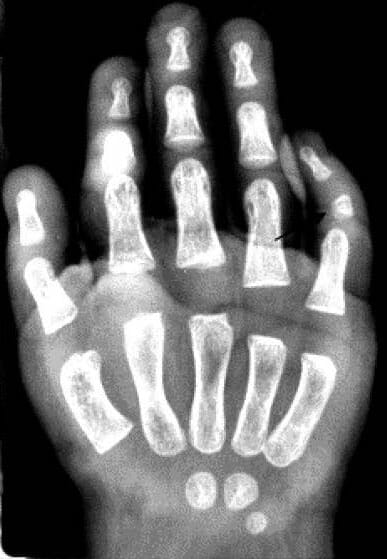

現在、24か月時点で、患者は発育不全、体重10.6kg(5パーセンタイル値)、長さ78cm(5パーセンタイル値未満)、OFC 48cm(50パーセンタイル値)を呈している。 身体的特徴は、大きな前泉門および顔面外観のわずかな粗大化に対して有意であった。 鼻は短く、前捻鼻孔と滑らかな菌糸を有していた(図1-A)。 耳は正常に設定され、大きさおよび形状は正常であった。 口蓋は厚いガムで狭かった。 患者はまた、左足に第5指の斜指と多指症を呈した(図1-B、C)。

図1. 多発性先天異常。

(A)顔面のわずかな粗大化,鼻孔の前傾,滑らかな友好性。 耳は正常に設定され、大きさおよび形状は正常であった